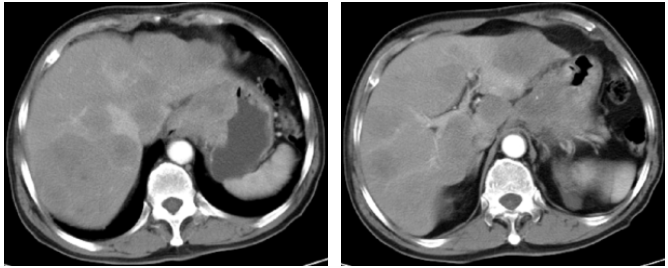

2022-4-13复查上腹部CT(3疗程后):符合贲门-胃体癌表现,伴肝内多发转移瘤,病灶均较前明显缩小,疗效评价PR。

该患者初诊为HER2阳性晚期胃癌伴肝、淋巴结多发转移,临床分期为cT4N2M1 Ⅳ期,分子病理检测结果为MSS、PD-L1阴性(CPS=0)。根据2021版CSCO胃癌诊疗指南推荐,晚期HER2阳性患者,1A推荐曲妥珠单抗联合奥沙利铂/顺铂+5-FU/卡培他滨方案。基于KEYNOTE-811研究的初步疗效数据,美国FDA在2021年5月份,就已加速批准帕博利珠单抗联合曲妥珠单抗+化疗,一线治疗HER2阳性胃/胃食管连接癌的适应证。针对本例患者,为了追求更有效的治疗效果,尝试使用曲妥珠单抗、PD-1单抗联合化疗治疗,3周期后影像学评估PR,疗效显著,不良反应可控,说明曲妥珠单抗(汉曲优)联合抗PD-1单抗治疗的疗效显著及安全性良好。

本病例中,患者为HER2阳性、MSS、PD-L1阴性(CPS=0)晚期胃癌,为了追求更好的治疗效果,参考KEYNOTE-811研究的治疗方案,结合患者的分子病理特征与实际情况,患者最终治疗方案为曲妥珠单抗(汉曲优)+PD-1单抗+卡培他滨+奥沙利铂。治疗3个疗程后,患者肿瘤标志物降至正常,影像学疗效评价PR。治疗过程中仅观察到胃肠道反应,心脏、肝肾功能毒性及免疫治疗相关毒性均未出现,安全性可控。结果证明汉曲优在HER2阳性晚期胃癌患者治疗上疗效显著,安全性良好,临床上可以替代使用。